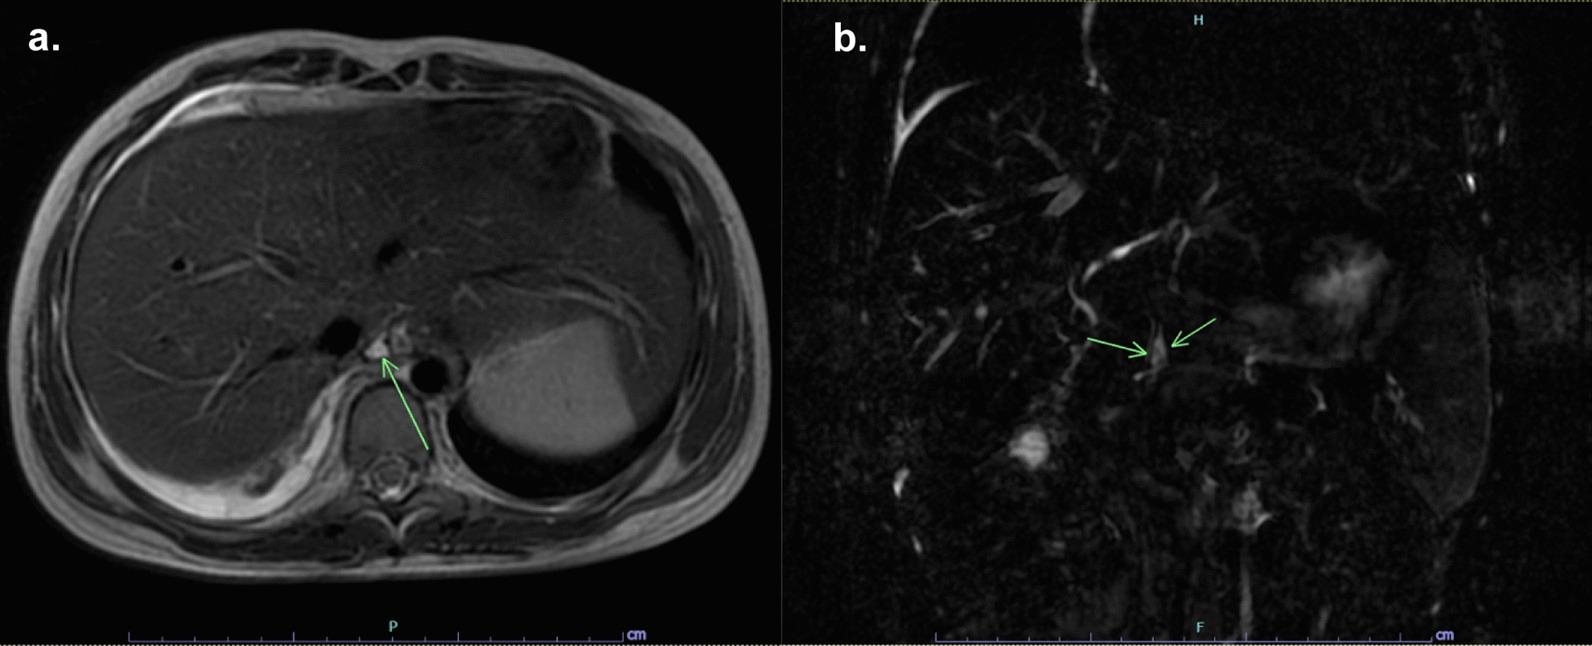

Pancreaticopleural fistula (PPF) is a rare complication of chronic pancreatitis (CP) that requires a high index of clinical suspicion in the patient who presents with a pleural effusion. Visualizing the fistula tract from the pancreatic duct to the pleural space by radiological imaging provides confirmation of this complication.

PPF is a rare but serious complication of CP in all ages. The diagnosis of PPF in children requires a high index of clinical suspicion and should be considered in the differential diagnosis of massive pleural effusion where pancreatic pathology is present. A high level of pleural fluid amylase and the results from radiological imaging when the patients have symptoms play essential roles in the diagnosis of PPF. Currently, Magnetic resonance cholangiopancreatigraphy (MRCP) is the imaging modality of choice. Endoscopic therapy and surgery are treatment options for patients who do not respond to conservative therapy.